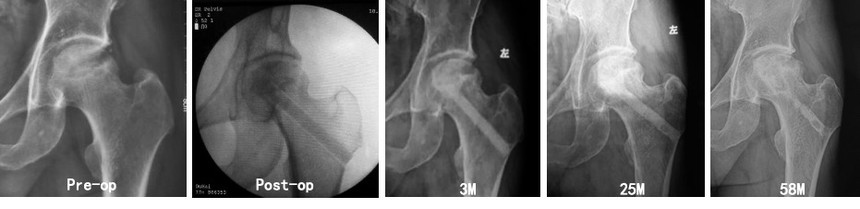

陶瓷棒技术保髋治疗酒精性股骨头坏死(男性,46岁,ARCO III) 术前HHS 73分,术后1年HHS 94分。 植入材料:陶瓷棒,10*80mm,1根 + 不规则多孔颗粒,直径 1.0-3.5mm,6g 上一篇股骨头坏死(陶瓷棒技术)下一篇股骨头坏死(陶瓷棒技术) |